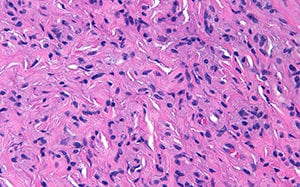

El informe histopatológico, reveló microscópicamente la presencia de una lesión polipoidea revestida de epitelio escamoso sin atipias y subyacentemente ocupando la totalidad del corion una proliferación difusa sin formación de plexos , constituida por células de citoplasma mal definido y bordes mal delimitados que contienen unos núcleos pequeños ondulados y con proliferación fibrilar, siendo el diagnóstico de neurofibroma solitario (Figura 6-8).